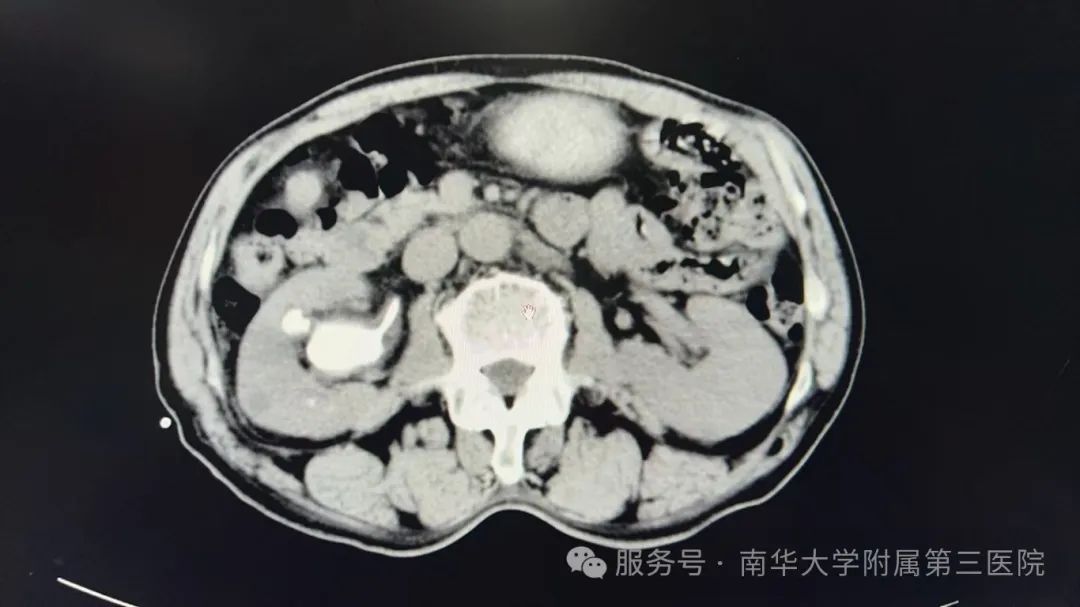

经过一系列详细检查,南华附三医院泌尿外科主任刘明诊断老王患有复杂性鹿角状肾结石,手术难度大且风险较高。面对这一挑战,老王表示充分信任医生,愿意积极配合治疗。随后,刘明与老王及其儿子进行了充分的沟通,详细告知了手术风险及可能的后遗症,并征得了他们的理解和同意。

手术采用经皮肾镜联合输尿管软镜碎石取石术,这一联合手术方式相当于在肾脏的“两端”同时开工,力求将结石彻底清除。手术过程中,老王需要摆成特殊的“骑马射箭位”,以确保手术操作的顺利进行。手术由院长助理徐兵和刘明主任联合主刀,在手术麻醉科医护人员的紧密配合下,为时三个小时的手术圆满成功。